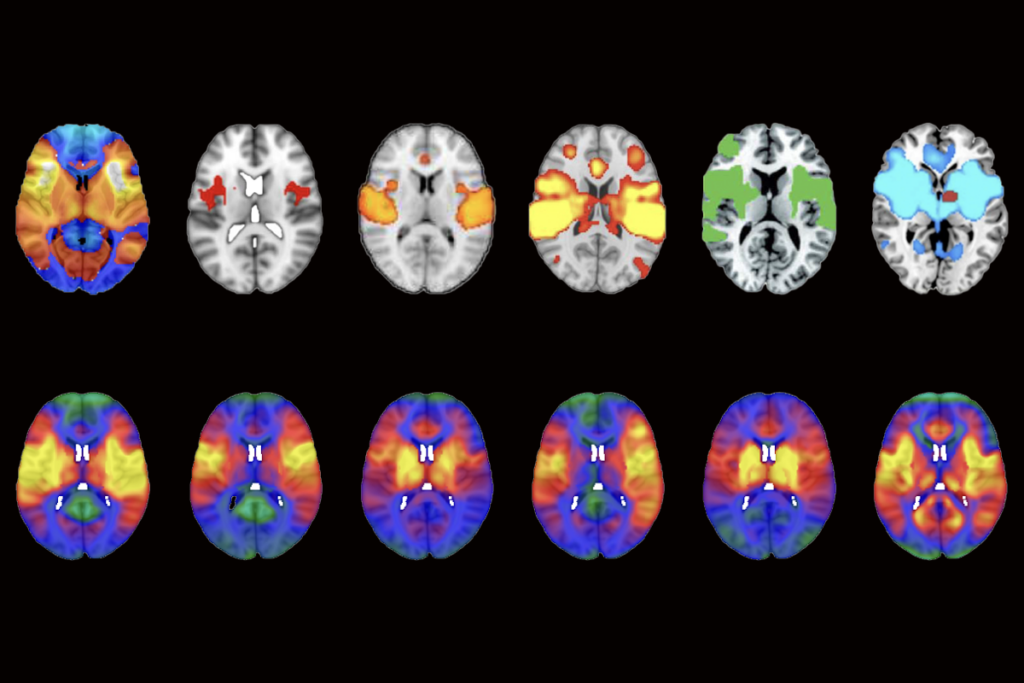

IQ’s link to brain structure, function in children may be a mirage

A child’s socioeconomic status, screen time and amount of sleep all show stronger associations with measures of brain structure and function, according to an imaging study of nearly 12,000 9- to 10-year-olds.

IQ’s link to brain structure, function in children may be a mirage

A child’s socioeconomic status, screen time and amount of sleep all show stronger associations with measures of brain structure and function, according to an imaging study of nearly 12,000 9- to 10-year-olds.

‘Overdue’ debate unfurls over neuroimaging method

After a January paper questioned the validity of an approach called lesion network mapping, its users are pressure testing their results.

‘Overdue’ debate unfurls over neuroimaging method

After a January paper questioned the validity of an approach called lesion network mapping, its users are pressure testing their results.

Methodological flaw may upend network mapping tool

The lesion network mapping method, used to identify disease-specific brain networks for clinical stimulation, produces a nearly identical network map for any given condition, according to a new study.

Methodological flaw may upend network mapping tool

The lesion network mapping method, used to identify disease-specific brain networks for clinical stimulation, produces a nearly identical network map for any given condition, according to a new study.